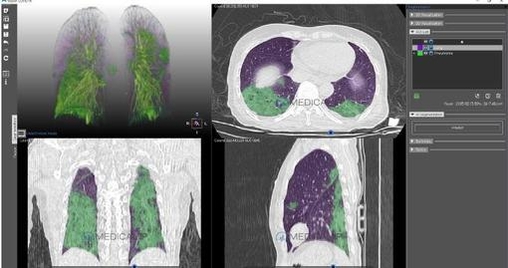

앞서 소개해드린 기술이 코로나19 확진 여부를 진단하는 AI였다면, 지금 만나볼 것은 확진자의 폐렴 중증도를 가려내는 AI입니다. 이미 여러 언론 매체를 통해 보도되었듯, 코로나19는 경우에 따라 중증 폐렴을 유발하기도 합니다. 따라서 확진자의 폐렴 상태 경증을 확인하는 것이 매우 중요하지요. 이를 위해 우리나라의 의료용 3D 프린팅 전문 기업이 'MEDIP PRO'라는 기술을 개발했습니다. AI가 CT, MRI 같은 2차원 의료 영상 데이터를 분석해 3차원으로 변환해주는 기술입니다. 체내 곳곳을 보다 입체적으로 살펴볼 수 있게 해주는 것이에요.

서울대학교병원, 중국 란저우대학제1병원, 일본 국군중앙병원 등 한중일 공동 연구팀은 미국 내 국제 의료 학술지를 통해 이 기술을 긍정적으로 평가했습니다. 특히 CT와 MRI로는 알기 어려웠던 확진자의 구체적인 폐 손상 상태가 3차원 데이터에서 매우 정확히 측정되었다고 합니다.